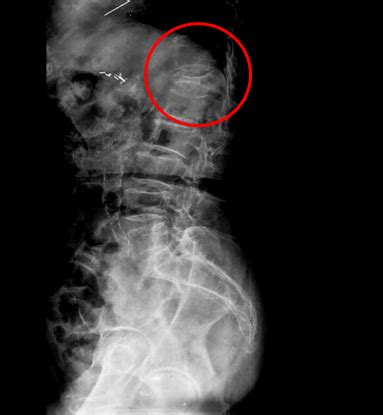

交通事故尾骨骨折可以评残不

单单尾骨骨折是够不上人体损伤的伤残等级的。

交通事故造成尾骨骨折是否能定残?能定的话是几及?

一般这样,如果对生活影响不大,找点关系一般能定10级。